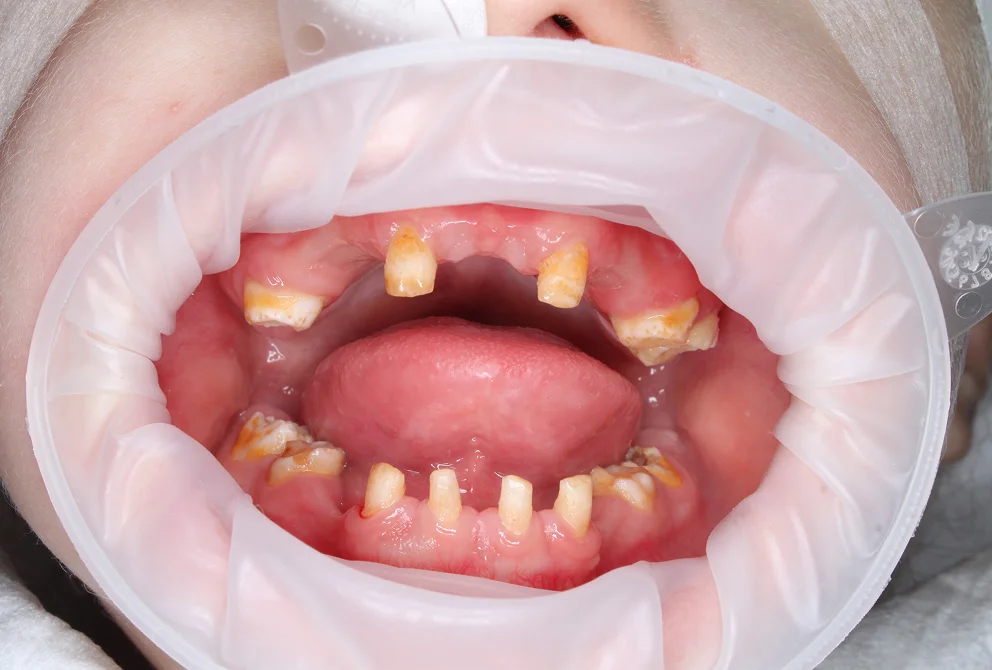

Пороки твёрдых тканей: дифференциальная диагностика

Молярно-резцовая гипоминерализация (MIH), флюороз, несовершенный амелогенез, дисплазии дентина — клинические признаки каждого состояния и границы между ними. Классификация Wuerzburg 2.0. Дисплазии дентина: от облитерации пульповой камеры до «зубов-призраков».

Реставрация зубов с пороками твердых тканей: адгезия, материалы, протокол.

Особенности адгезии к гипоминерализованной эмали и изменённому дентину. Критерии выбора между прямой и непрямой реставрацией.